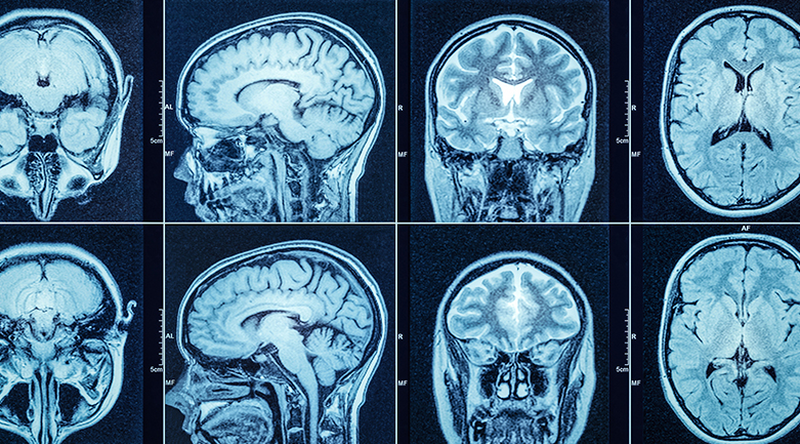

Chụp CT cắt lớp khi nào? Những rủi ro khi dùng thuốc cản quang 1Chụp CT cắt lớp tạo ra hình ảnh các cơ quan, các mô, xương theo lát cắt ngang

Chụp CT cắt lớp là kỹ thuật kết hợp tia X và máy tính để tạo ra hình ảnh các cơ quan, các mô của cơ thể, xương theo lát cắt ngang. Những hình ảnh chụp CT cung cấp nhiều thông tin chi tiết hơn so với hình ảnh từ phương pháp chụp X-quang thông thường. Chúng có thể hiển thị các mạch máu, mô mềm và xương ở các bộ phận khác nhau của cơ thể như đầu, vai, ngực, bụng, xương sống, tim, đầu gối…